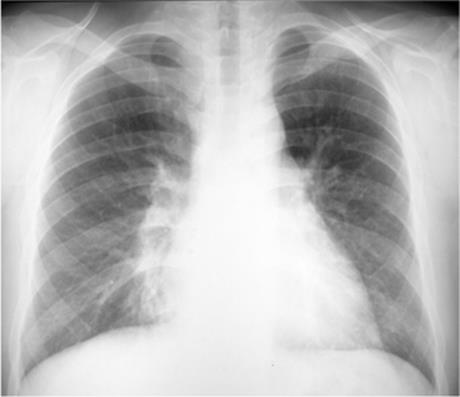

Focal opacity may be visible, especially when comparing one lung with the other on the frontal projection. On the lateral projection attention should be directed over the thoracic spine, the cardiac silhouette, and the retrosternal and retrocardiac regions, where faint opacity may otherwise escape detection (Figs. 5.1 and 5.2).

Figure 5.1 Opacity in pneumonia. (A) Posteroanterior and (B) lateral chest radiographs: minimal right basilar opacity, much better seen on the lateral view overlying the heart (P).